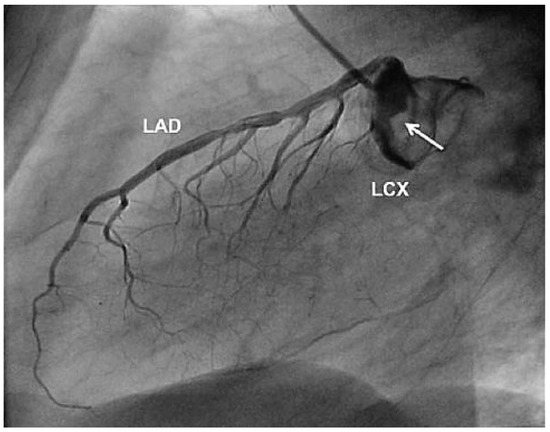

Aneurysm of the Left Circumflex Coronary Artery

by Christian Arranto, Christoph Auf der Maur and Paul Erne

Cardiovasc. Med. 2010, 13(7), 247; https://doi.org/10.4414/cvm.2010.01511 - 11 Aug 2010

Abstract

A 54-year-old man was hospitalised because of an inferior ST-elevation myocardial infarction [..] Full article